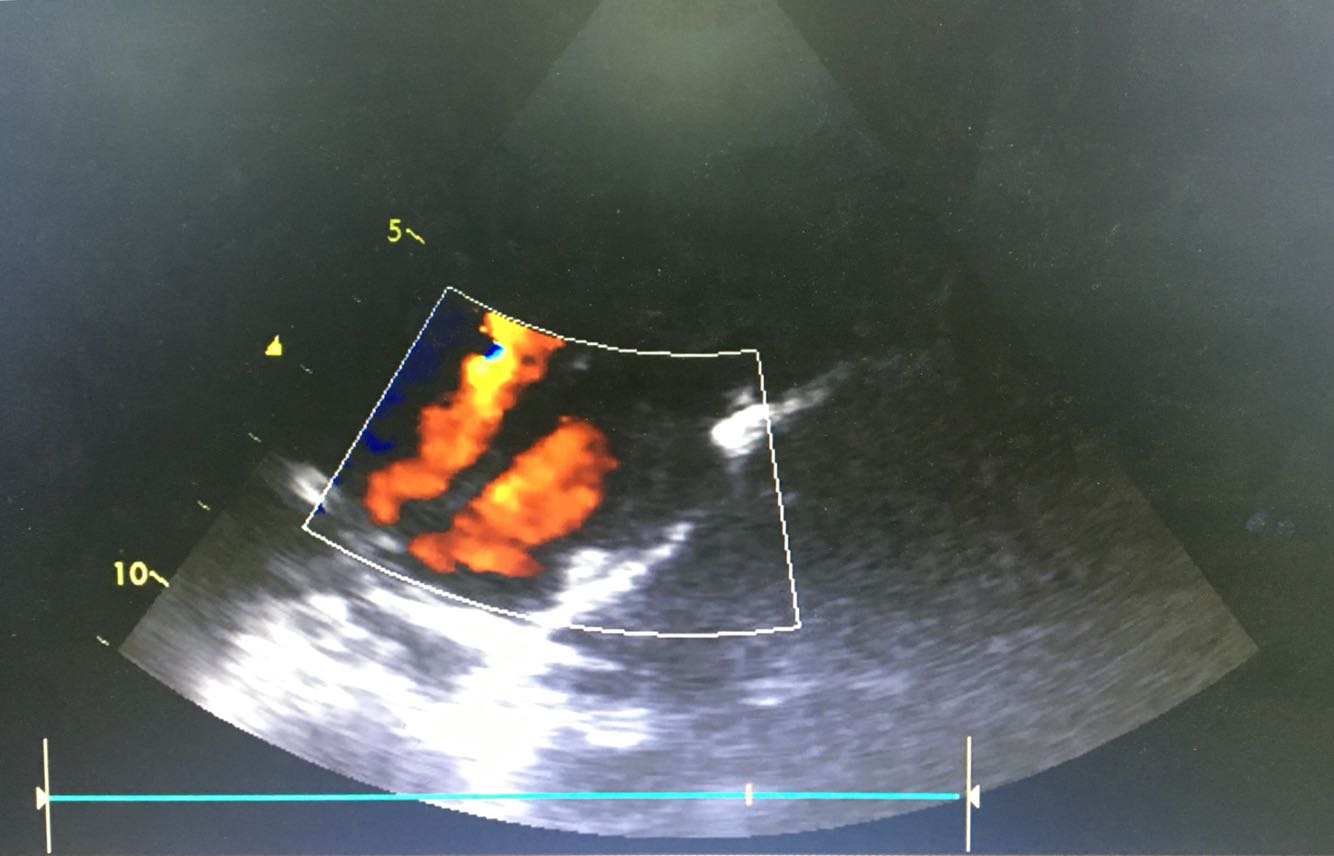

查体:神清,精神稍微疲软,发育正常,皮肤及巩膜无黄染,无淤血淤点,无发绀,浅表淋巴结未及肿大,口腔黏膜光整,咽不充血,双扁桃体I度肿大,颈软,气管居中,双肺呼吸音粗,未及明显干湿罗音,心率120次/分,律齐,无杂音。腹平软压痛及反跳痛,未及明显肿块,肝肾叩击痛(-),移动性浊音阴性,神经系统检查(-)。